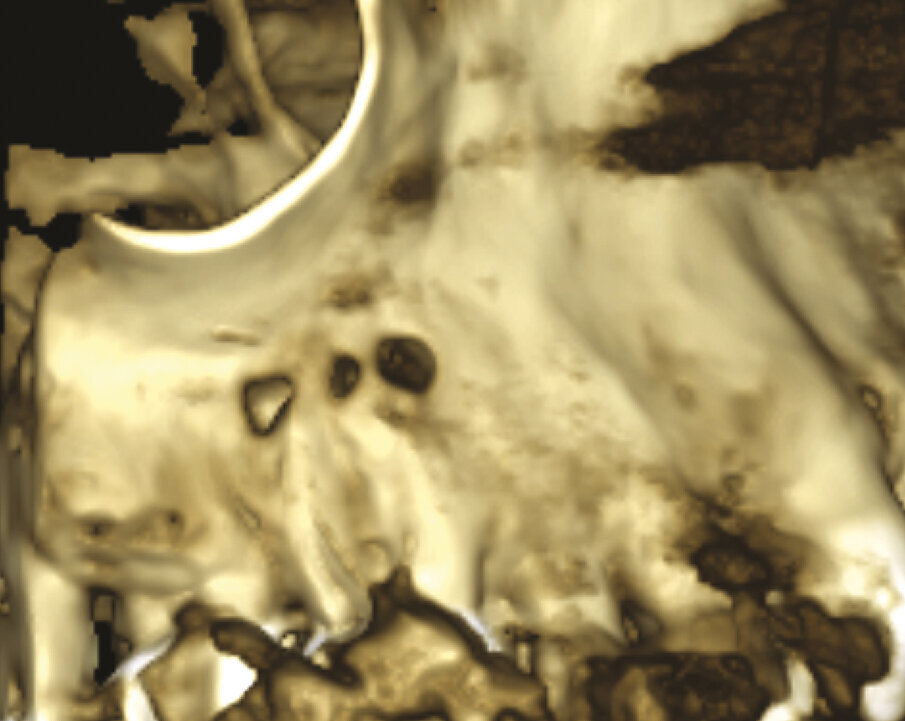

Fig. 1a - Il paziente è stato inviato per la terapia chirurgica della radice mesiovestibolare del primo molare superiore di destra.

Fig. 1b - Una radiografia presa con diversa angolazione sembra confermare che l’unica radice coinvolta nella lesione periapicale è la mesiovestibolare.

Fig. 1c - La CBCT mostra il riassorbimento dell’osso corticale adiacente la radice distovestibolare.

Figg. 1d, 1e - Un’altra lesione periapicale sta interessando il secondo molare.